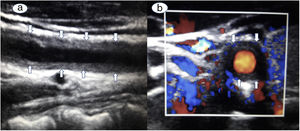

An 18-year-old female presented with complaints of low-grade fever, easy fatigability, claudication pain in all four limbs and transient loss of vision in both eyes for last 6 months. On evaluation, she was found to have absent all peripheral pulses along with bruit over the bilateral carotid artery, bilateral subclavian artery, over back in the mid-scapular region and left renal artery. On ultrasound B mode scanning of the right carotid artery on longitudinal [Fig. 1a] and transverse [Fig. 1b] cuts, showed homogenous, mid-echoic, circumferential wall thickening, a rare but pathognomonic sign of Takayasu arteritis known as ‘Macaroni sign’. Similar findings were present on the left side also. This uncommon ultrasonography finding was first described by Maeda et al.1